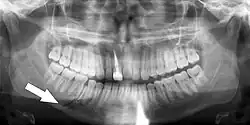

Root fracture

Simple mandible fracture